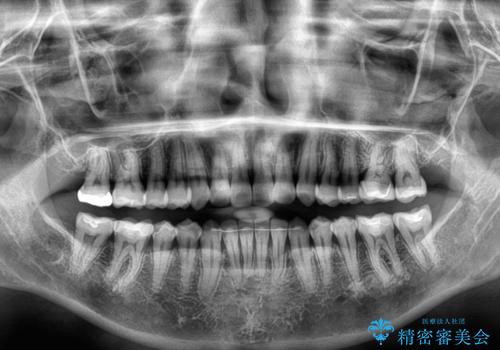

クロスバイトを治したい インビザラインによる矯正治療

- 前歯のクロスバイトを気にして来院された患者様です。

上下ともに、前歯部を中心にやや叢生が認められる程度であったため、ワイヤーでもインビザラインでも、どちらでも対応可能な状態でした。

咬合力が非常に強く、治療が進むにつれて上下奥歯が離開してくることが予想されるため、治療途中から上下の顎間ゴムを使用することを理解いただき、インビザラインによる矯正治療を行うこととしました。

咬合力による臼歯離開は顎間ゴムで改善されましたが、それとは別に下顎小臼歯がマウスピースに追従せず、補正のためのゴムかけが必要となりました。

大変なゴムかけ作業を頑張っていただき、無事に治療を終えることができました。